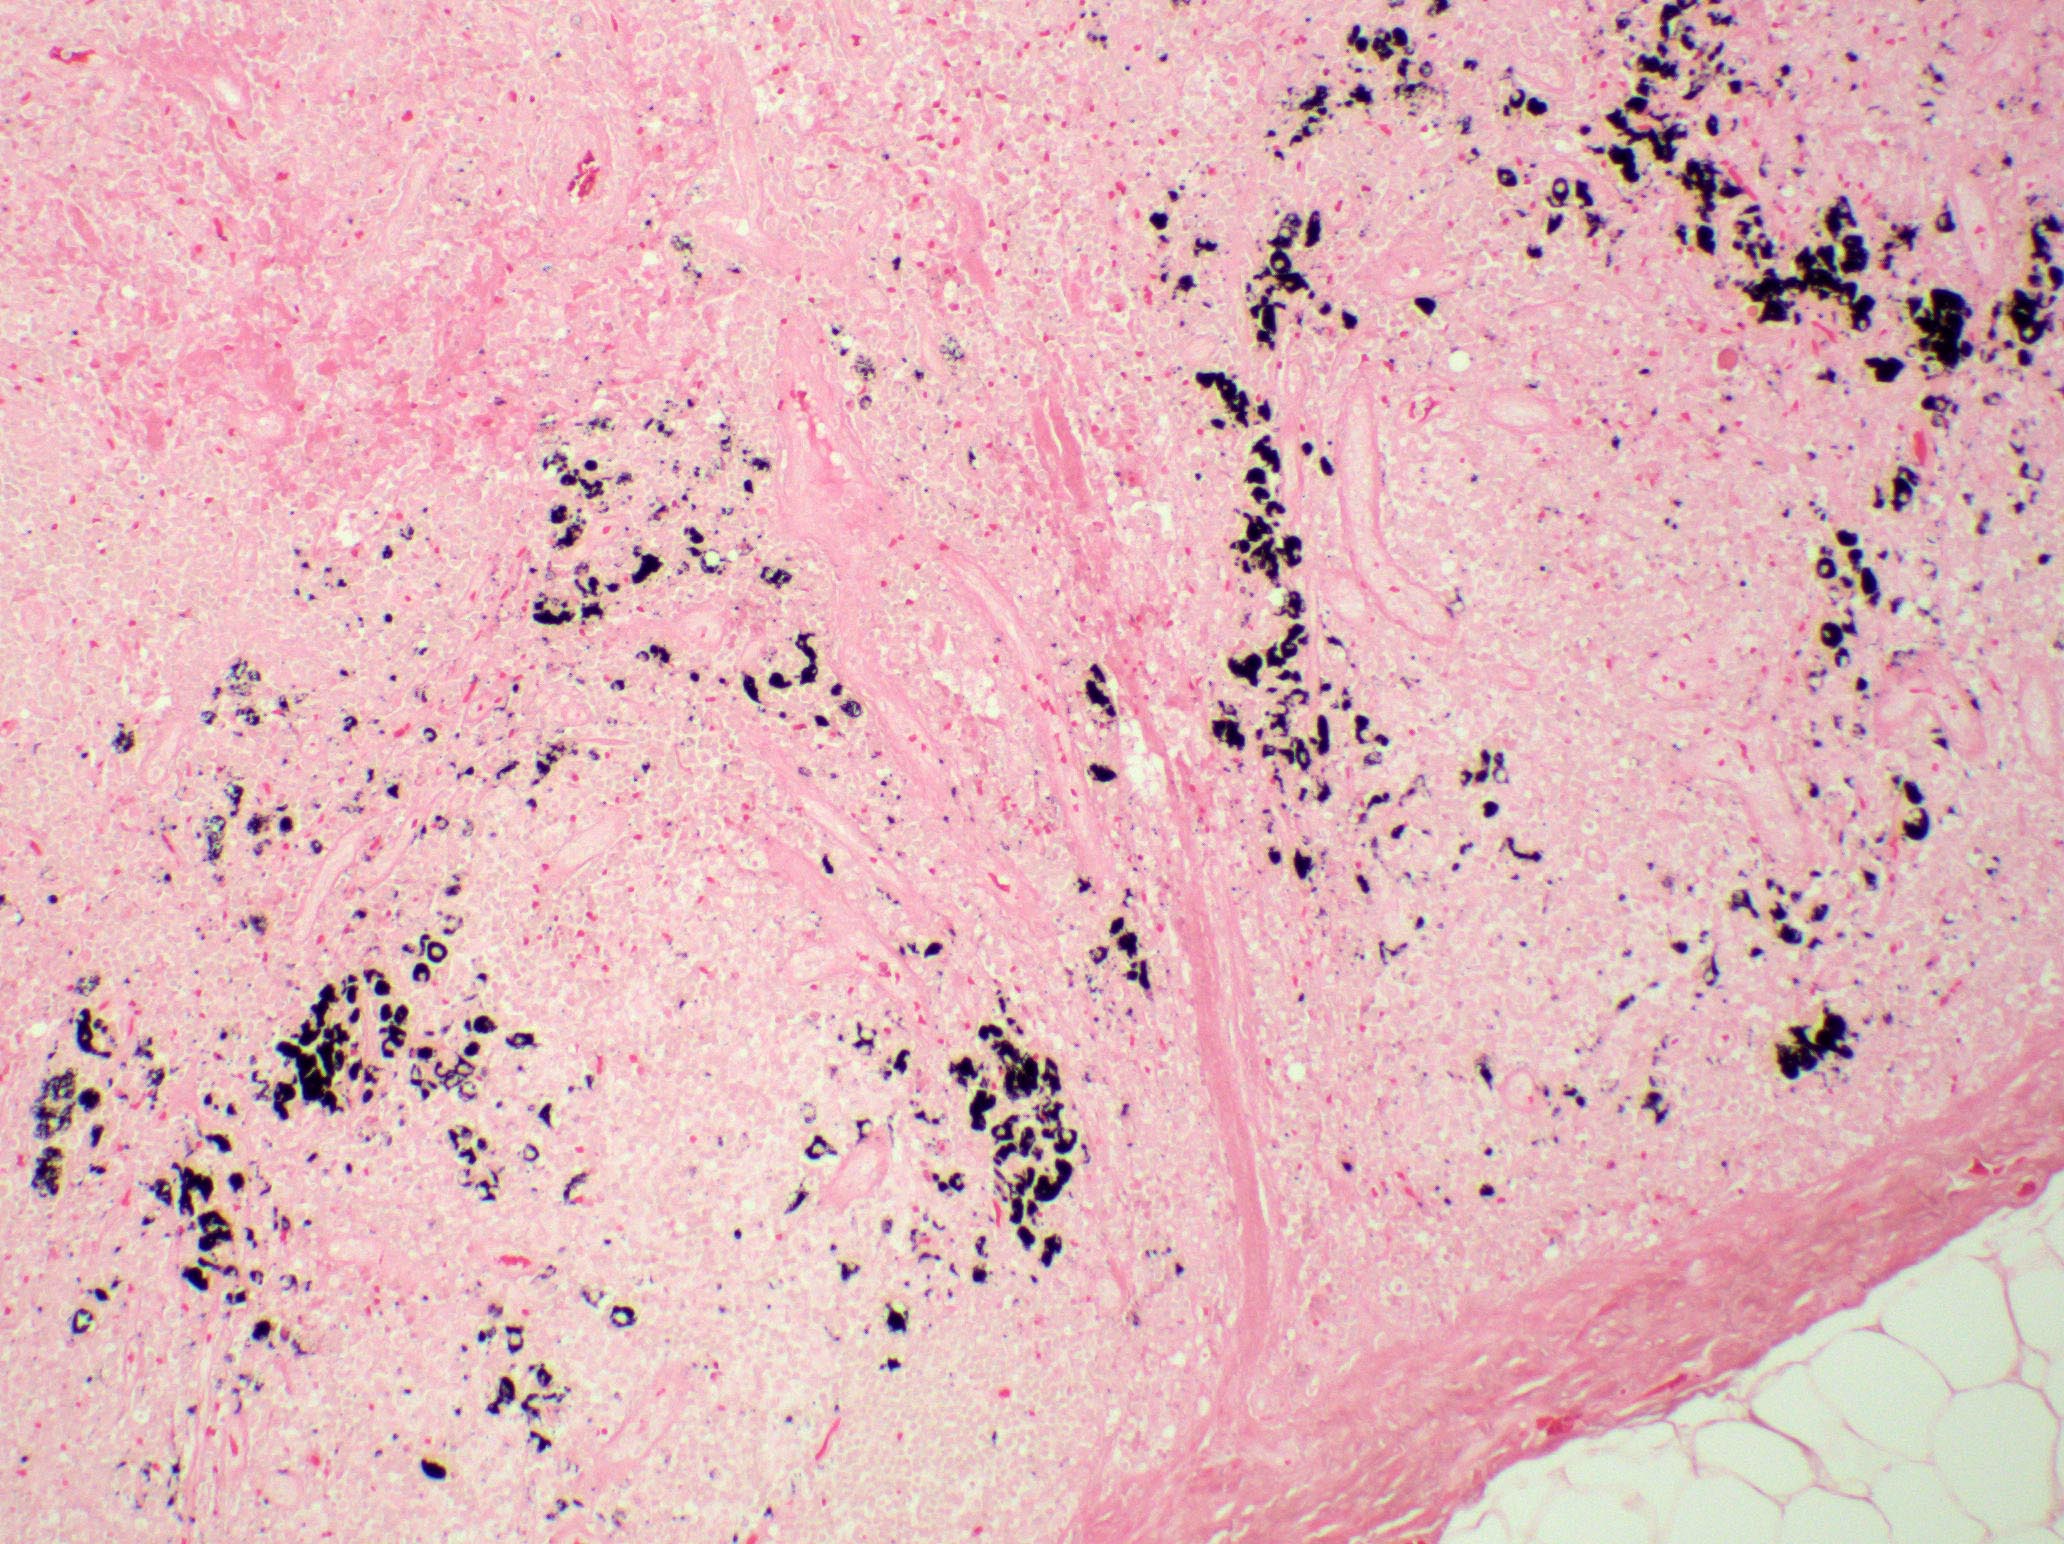

Microscopic (histologic) description

- Paracortical or sinusoidal histiocytes and macrophages often contain cytoplasmic melanin pigment but they also can contain hemosiderin or lipid

Microscopic (histologic) images

Contributed by Ingrid Tam, M.D., M.Sc., Emina Emilia Torlakovic, M.D., Ph.D. and Nikhil Sangle, M.D. (Case #396)

Positive stains

- Fontana-Masson silver stain for melanin; melanin histochemical stain is often positive even when melanin is not readily identified on H&E sections